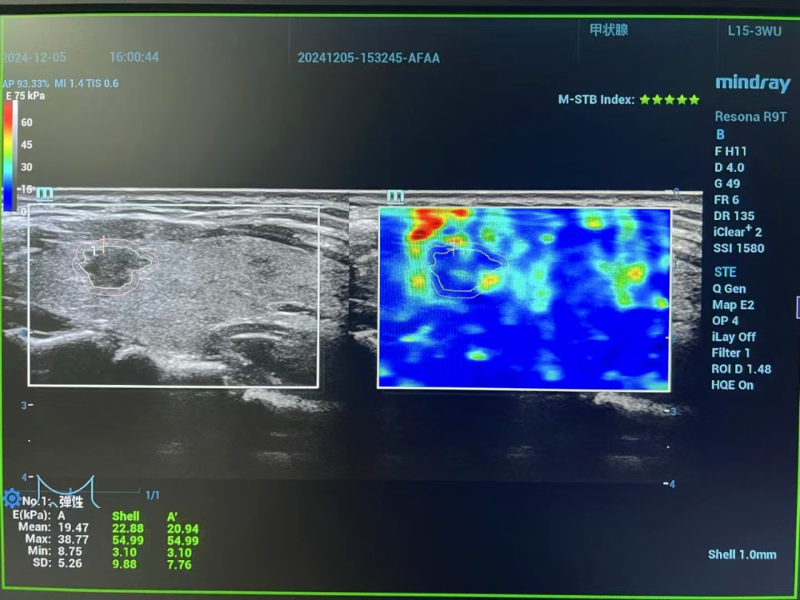

△术前评估

术前评估阶段,专家团队启用高分辨率颈部超声与先进磁共振成像技术,全方位、多维度扫描剖析。影像数据精准揭示:李女士左侧甲状腺结节小于1厘米,其包膜间距超2毫米,周边组织未现侵袭迹象,淋巴结转移亦无迹可寻。经严格筛选,甲状腺微小乳头状癌微波消融手术指征确凿无疑,为后续精准施治筑牢根基。